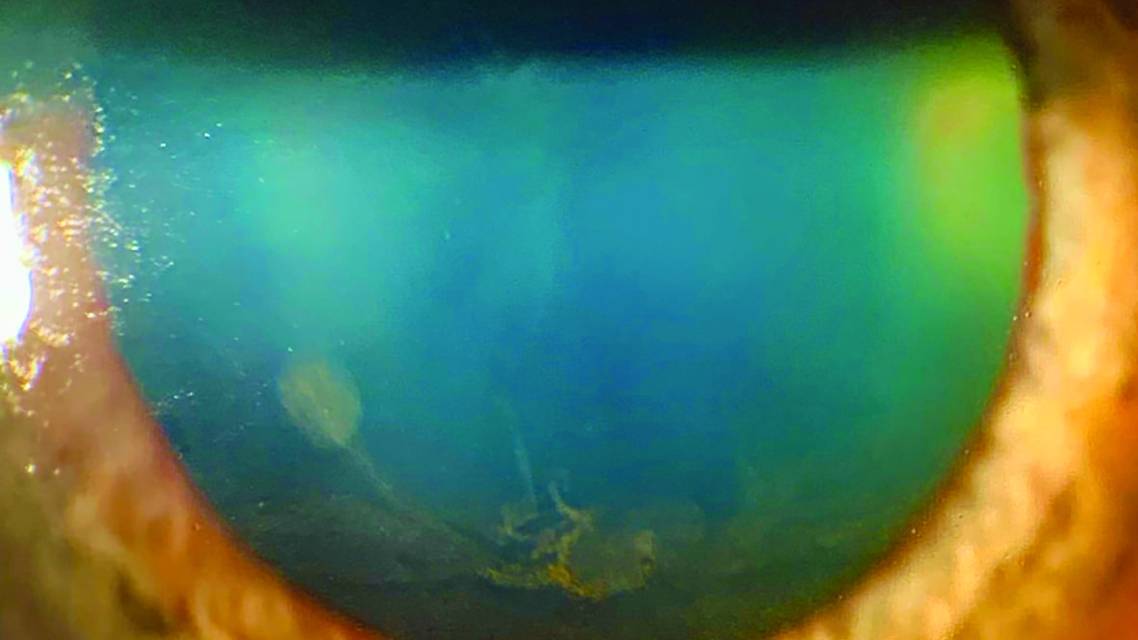

There are a multitude of differentials with regard to the corneal finding known as verticillate or whorl epitheliopathy (Figure). The standard acronym is CHAI-T+F (Chloroquine, Hydroxychloroquine, Amiodarone, Indomethacin, Tamoxifen, Fabry disease).

Corneal verticillata can appear for a host of reasons, including signs of serious underlying metabolic disease, such as Fabry disease and cystinosis. It can also occur as a side effect of certain medications, amiodarone being the most common. However, it is pertinent for eye care providers to consider glaucoma medications, specifically ROCK inhibitors, when investigating the source of this clinical finding.